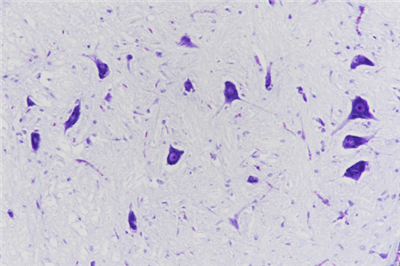

• 尼氏染色

尼氏染色:即Nissl染色法,用来鉴定神经元胞体中的尼氏体,是最常用的神经细胞染色,在该染色中,尼氏小体清晰可见,可区分轴突和树突等。